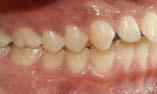

Figura 3. Primer aparto SN1 con almohadillas vestibulares. A. VF con aparato, B. VL derecha C. VL izquierda. D. SN1, vista oclusal (VO). Después de 7 meses del tratamiento se observa los avances obtenidos por el aparato y los ajustes del mismo los cuales observamos en las figuras: E. VO del SN1 7mm de crecimiento transversal, F. VF con aparato, 3G. VL derecha, H. VL izquierda.

Investigación clínica

Figura 4. Segundo Aparato SN1. A. VF con aparato, B. VL derecha, C. VL izquierda, 3D. SN1, VO. Después de 5 meses del tratamiento se observa los avances obtenidos por el aparato y los ajustes del mismo los cuales observamos en la imagen, E. VO del SN1 5 mm de crecimiento transversal, F. VF con aparato, G. VL derecha, H. VL izquierda.

Figura 5. Tercer aparato PIPS A. VF con aparato, B. VL derecha, C. VL izquierda, D. PIPS VO. Después de 7 meses del tratamiento se observa los avances obtenidos por el aparato y los ajustes del mismo los cuales observamos en la imagen, E. VO del PIPS sin los mantenedores de espacio, 5. VF con aparato, 5G. VL derecha, 5H. VL izquierda.

radiculares de O.D. 73 y 83 y rehabilitación oral completa de O.D. 54, 63,65 y 75. Se procedió a colocar aparatos ortopédicos para corrección de la maloclusión en enero del 2022.

El tratamiento inicio con AOF, SN1 con Equiplan adicionando almohadillas vestibulares en el maxilar para despresurizar la acción de la musculatura labial. La indicación de uso fue utilizarlo de forma continua solo retirándose para comer e higienizar, activar del tornillo tanto superior como inferior una vez a la semana, y se realizaron revisiones mensuales en la clínica para valorar avances, llevar

a cabo activaciones, ajustes del aparato e indicaciones. Como se observa en la Figura 3.

Al haber obtenido los avances programados en la corrección de la sobremordida vertical con esté AOF, se decide cambiar a un nuevo SN1, con equiplan sin almohadillas y con arco vestibular esto para continuar regularizando el plano de oclusión en el paciente, y fue utilizado por 5 meses de forma continua. Se mantuvieron las mismas indicaciones de uso, que en el aparato anterior. Como podemos observar en la Figura 4

El AOF Sn1 logró el avance mandibular, expansión programada, armonización de arcadas y regularización de la curva de Spee, entonces se determina cambiar dicho aparato por unas PIPS, clase I para mantener el espacio que corresponde a los O.D. 35 y 45, ya que fueron indicadas para extracción los O.D. 75 y 85, esperando la erupción de premolares para terminar el anclaje. Las indicaciones para el paciente fueron uso continuo de las PIPS por 3 meses, solo retirándose para comer e higienizar, revisiones mensuales en la clínica para activación y desgastes de los mantenedores de espacio, vigilando la erupción de los premolares. Posteriormente se indicó su uso nocturno por 4 meses más para mantener estabilidad de los resultados obtenidos.